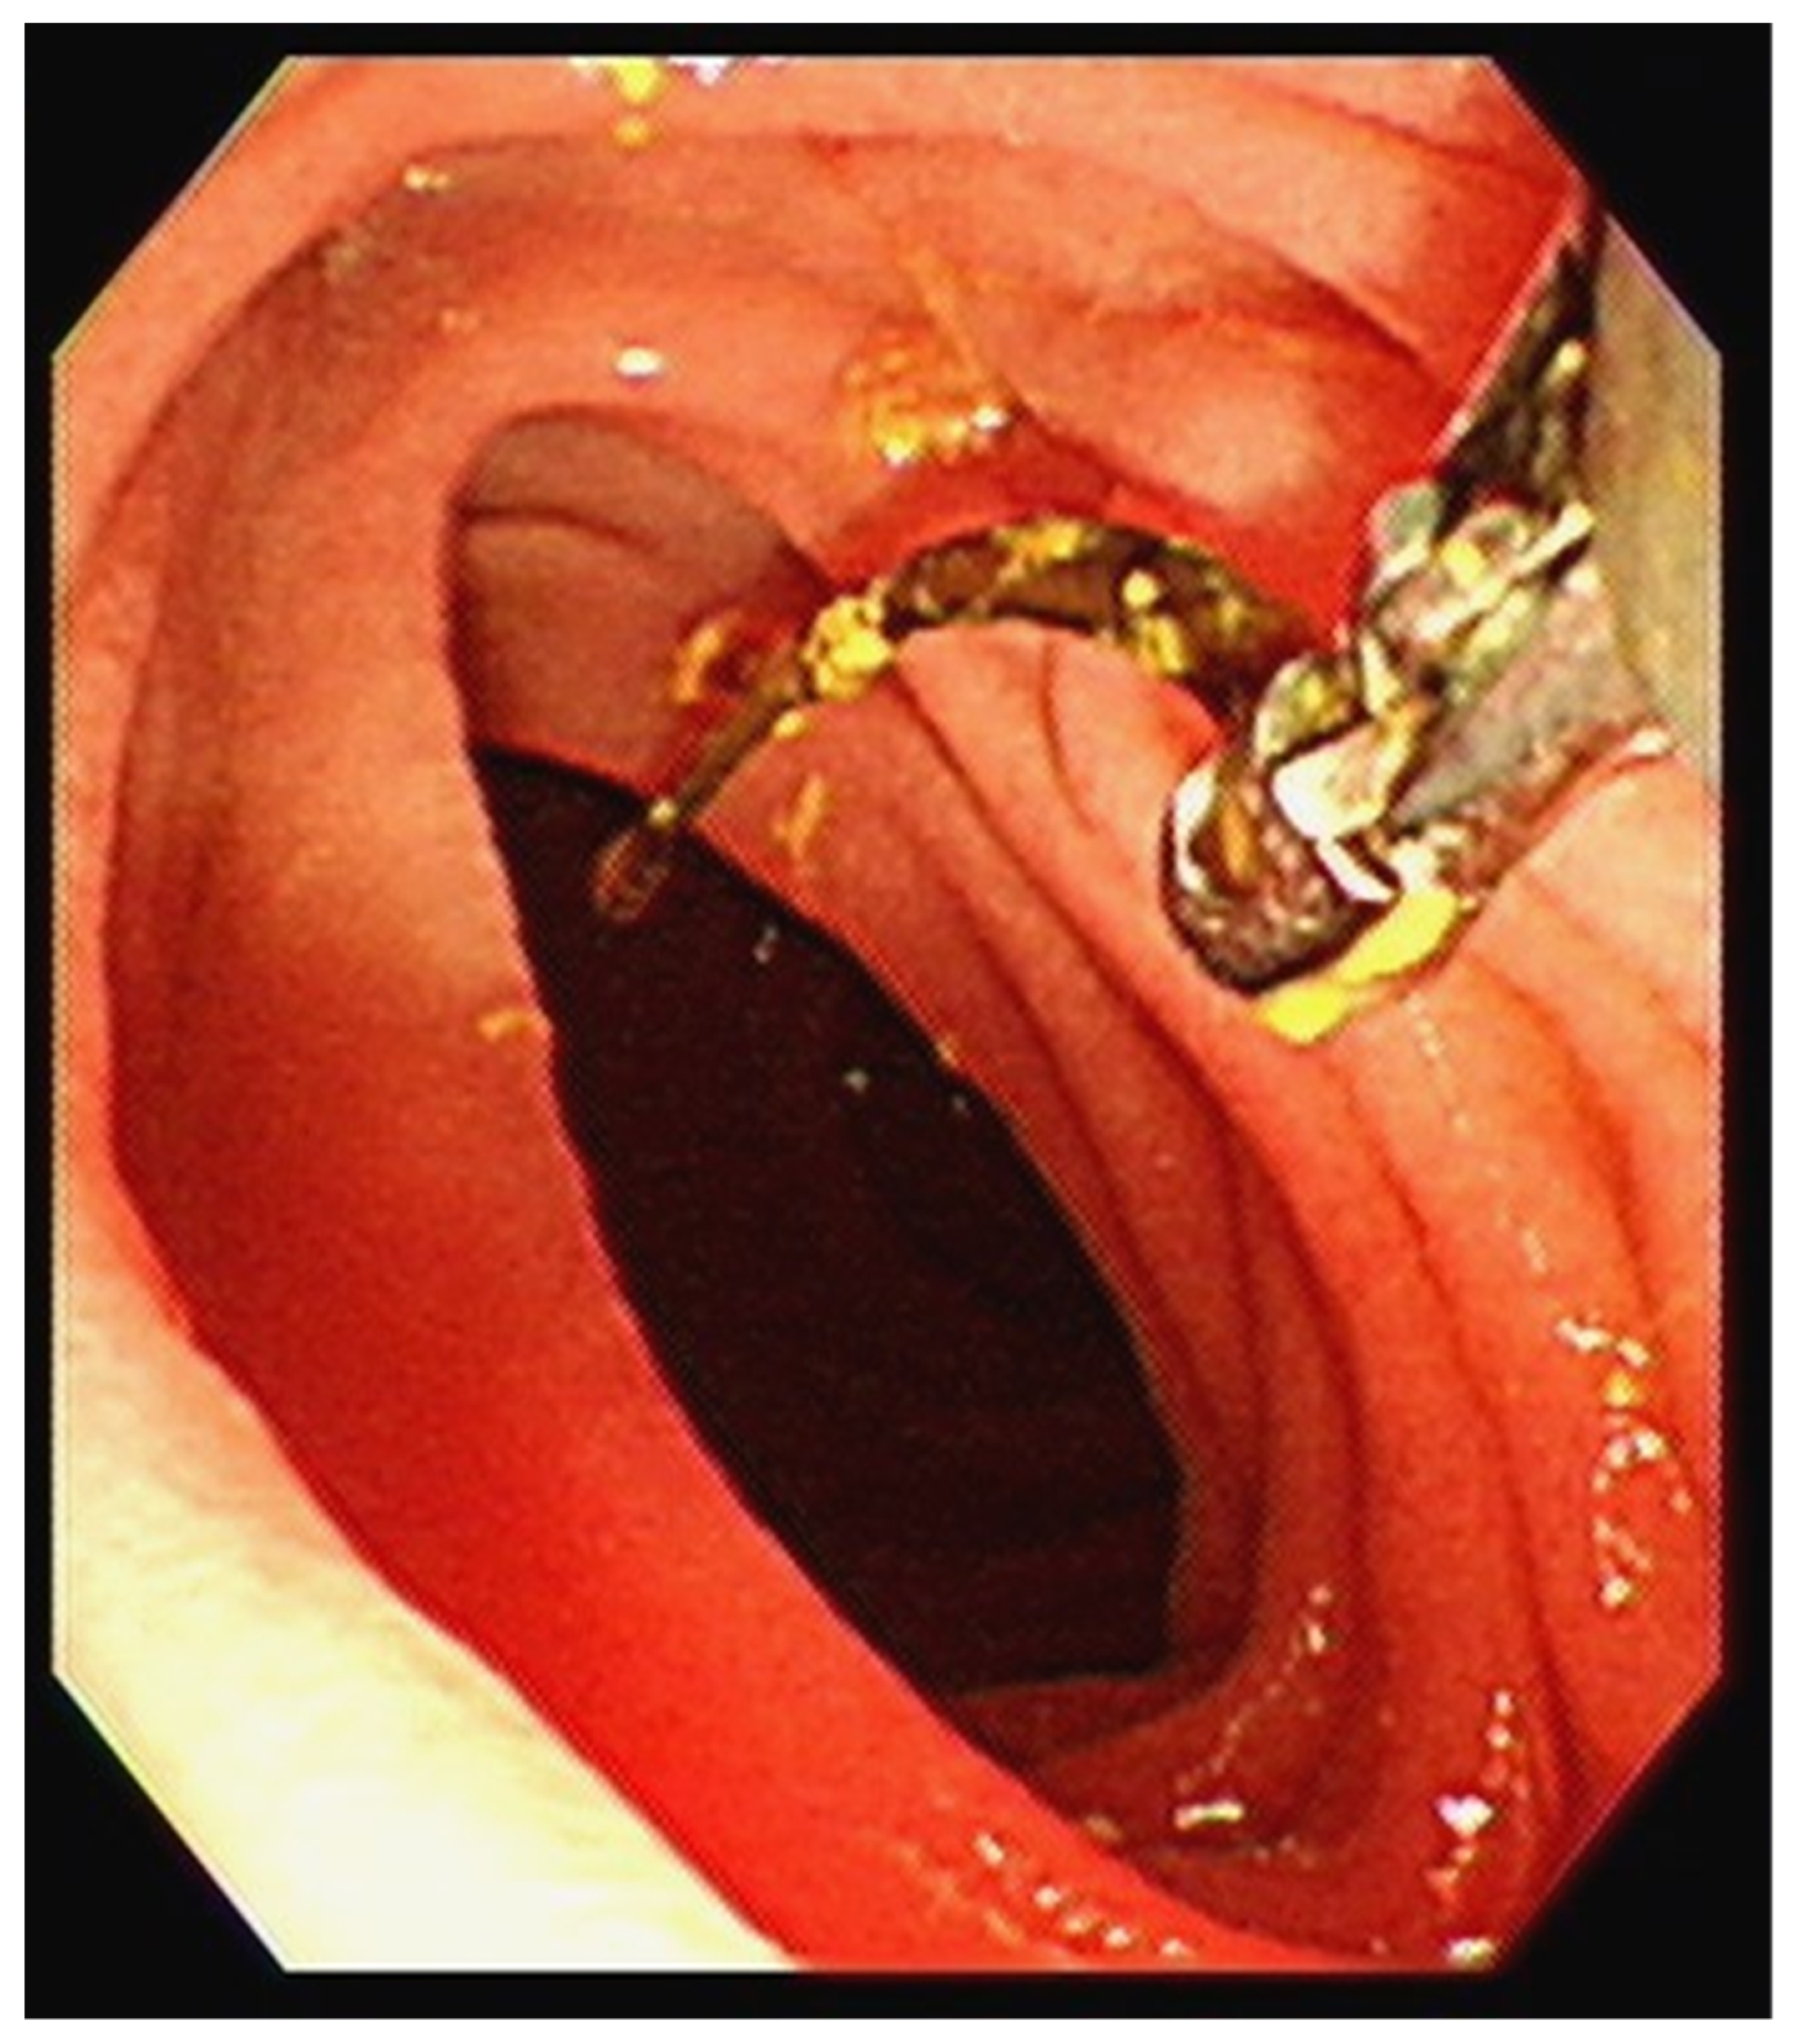

Figure 2. The patient underwent a biopsy, which revealed a 1.7 cm curved, linear, rusty, metallic surgical suture needle containing bile. A retained surgical item poses a hazard to surgical safety and occurs occasionally despite various systems and safeguards [1,2,3]. Any surgical material, including tools, supplies, and equipment, can inadvertently be left inside a patient’s abdomen and can cause subsequent harm to the patient. Several factors increase the risk of the retention of surgical foreign bodies including patient characteristics such as obesity, case-specific conditions such as emergencies, complex surgical procedures, involvement of more than one surgical team, unplanned changes in the procedure, prolonged surgical procedures, and operating room’s culture and environment [4]. Intraoperative and postoperative imaging may assist in the rapid identification of the site of foreign bodies, as it did with our patient’s retained needle [5]. Although radiography easily detects retained surgical needles longer than 1 cm, the detection of smaller needles less than 1 cm in length is more difficult [6]. Compared with plain radiography, abdominal CT can provide more accurate findings.